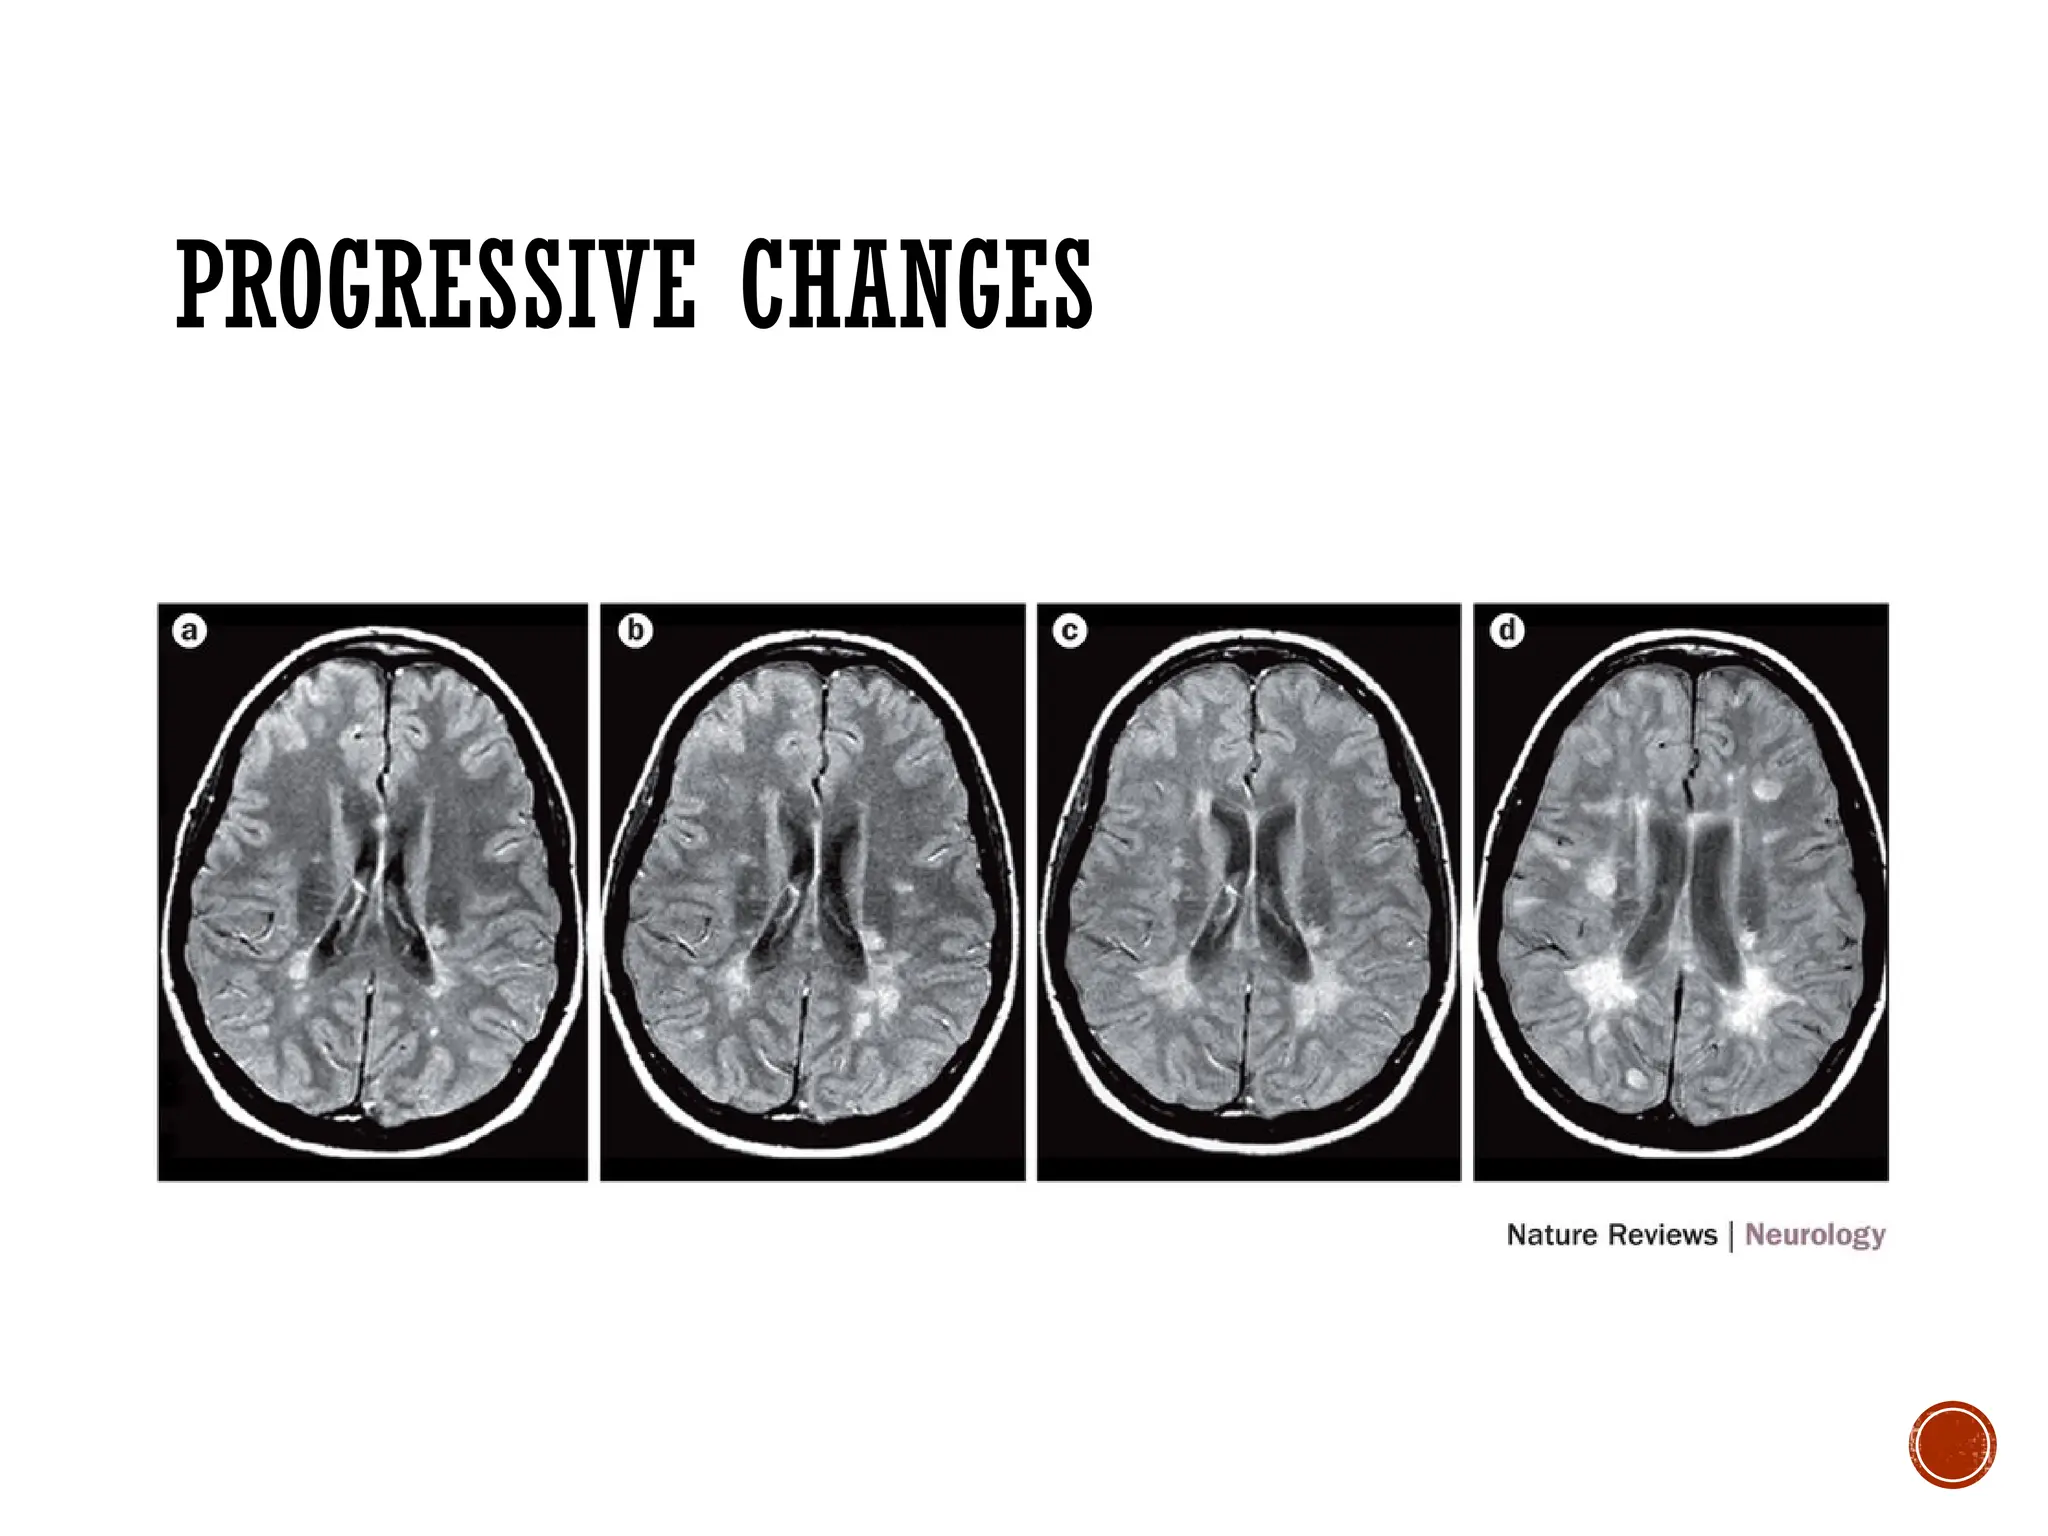

PROGRESSIVE CHANGES

MS is an ongoing process of demyelination,

remyelination, and eventual neuron loss

Relapses & Remissions: Most MS

sufferers experience periods of acute

exacerbations (flares, relapses) varying in

number and severity, followed by periods of

remission, where all symptoms

spontaneously cease: inflammation

damage to CNS is continuous, occurring

during flares AND remissions